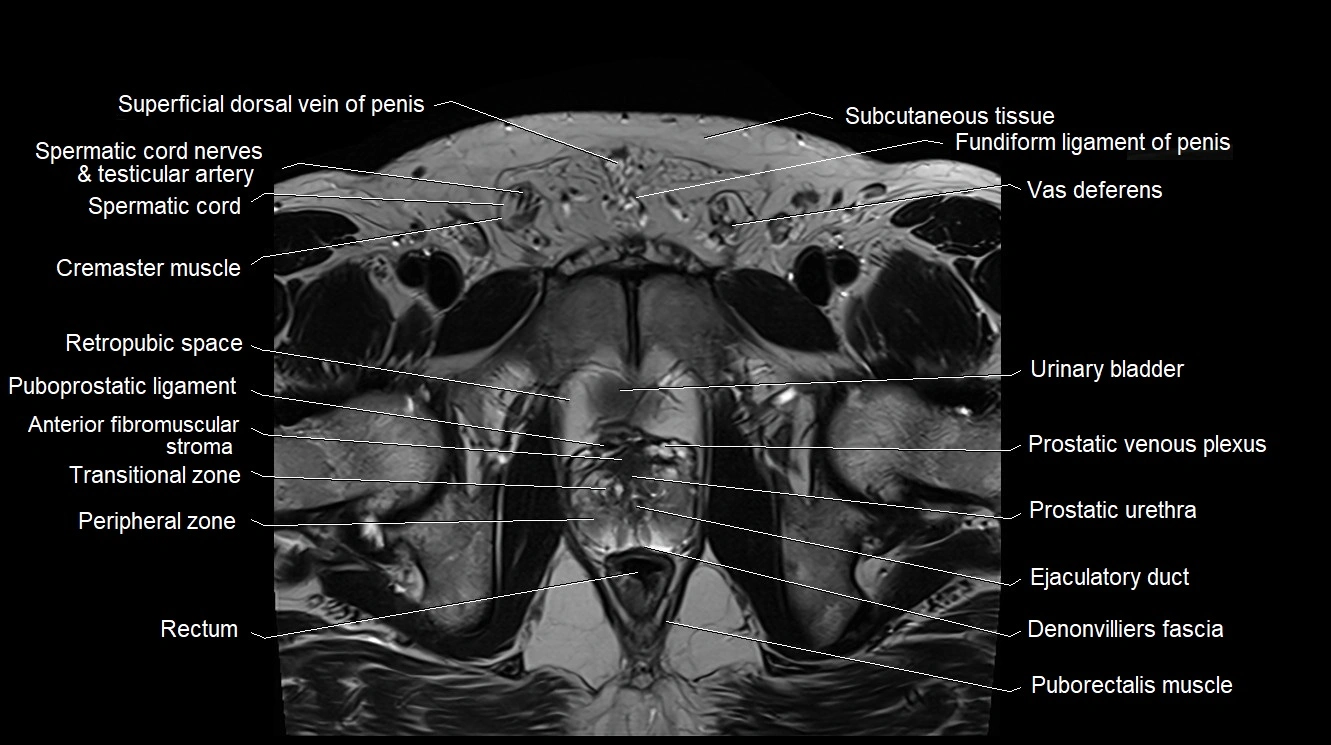

MRI image